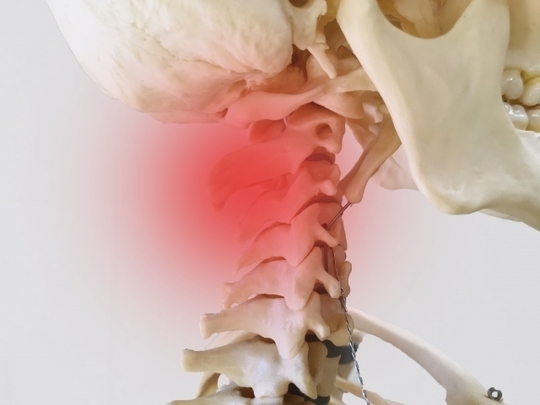

頭痛は頸椎に異常があり手指で圧迫すると痛みがあることがほとんどですが、頸椎の2番と3番の圧迫痛を消去すると頭痛が治ります。交通事故のむちうち症の場合は特に著明です。また首の筋肉も緊張し固くなっています。頭蓋骨と首の境目が凝っていることがほとんどです。

赤い部分が頸椎の2番と3番の境目です。頭痛が発症している場合はこの部分を指で押すと痛みがあり、圧迫痛を除去すると回復に向かい頭痛は治癒します。